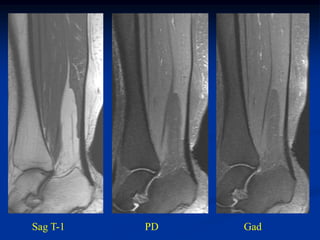

Case #1190.2

33 year old female with

painless lump at ankle

for 1 year

Sag T-1   PD   Gad